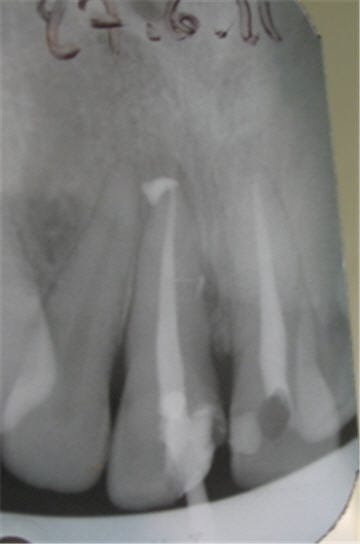

Il faut toujours essayer : parfois on est un peu sous gingival , ça à l'air mal barré et puis on met la digue et hop : magie !!! cf photo ci-joint.

Digue si6cja - Eugenol